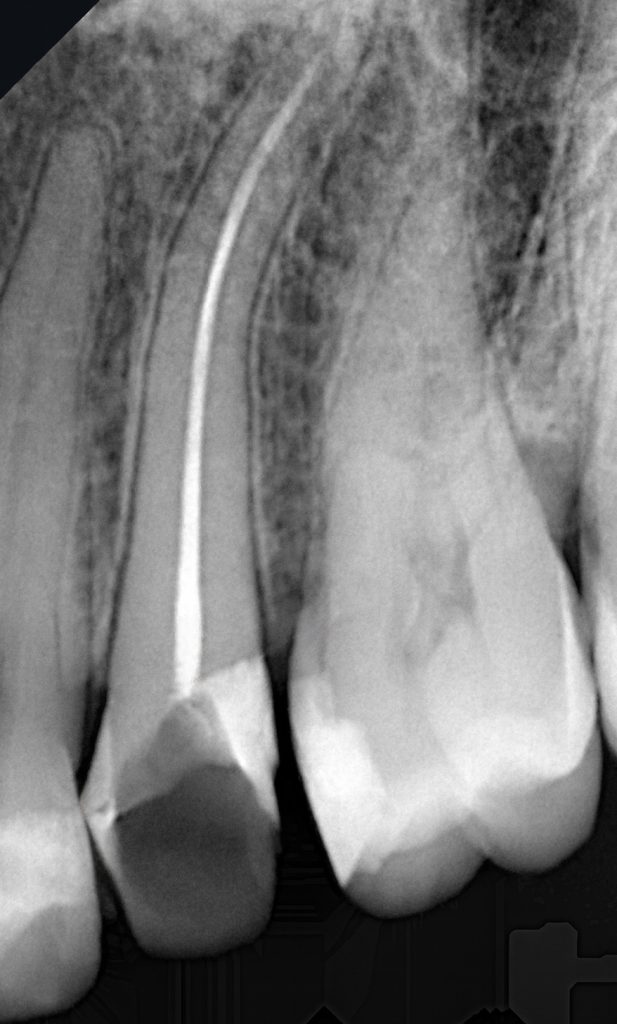

The patient presented with localized food impaction, deep caries in the lower right molar, and an endodontically treated premolar showing structural loss (Fig 1). A quadrant plan was developed to restore both teeth functionally and esthetically in a single session.

- Fig 1: Pre-operative quadrant showing caries and structural loss.